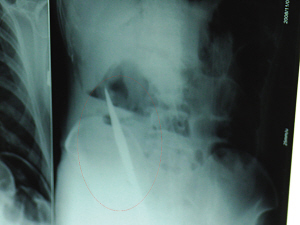

X光片上,尖刀清晰可见。

从男子体内取出的尖刀足足有19厘米长。

昨天上午,记者在徐州矿务集团总医院重症监护室见到了这名男子,目前他虽然已经恢复了意识,但还不能开口说话,需要呼吸机辅助呼吸。据医生介绍,4日中午12时左右,这名男子因服毒轻生被紧急送到医院进行抢救,之前,这名男子已经在当地乡镇医院进行了近20小时的治疗,但效果不佳。“病人被转院到矿总院时已神志不清,血压极低,处于休克状态。”救护人员给男子洗胃、初步处理以后,发现男子呼吸急促,于是赶紧给他拍片检查。结果让所有的医生大吃一惊,竟有一把尖状异物横在该男子腹腔内!当天下午5时30分,轻生男子被推上了手术台。经过40多分钟的手术,该男子腹腔被打开,手术医生发现,男子体内的金属状异物竟然是一把长19厘米的尖刀!

医生告诉记者,手术后,医生在病人身上并未发现刀痕,最后,经过检查发现,在该男子直肠处找到穿孔。医生从医学角度分析后认为,这把尖刀应该是从肛门插入直肠的。